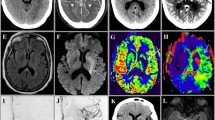

A 77-year-old lady, wake-up stroke, over 12 h from LKW with NIHSS 15. Automated eASPECTS analysis from Brainomix software (a), and source images (b) ASPECTS 8 with infarction in caudate and lentiform nuclei. Hyperdense right distal M1 segment (c) which reflects thrombus and corresponds to site of occlusion on CTA (d). Moderate collateral filling on phase 1 (not shown) but good collaterals on phase 2 images with branches filling back to proximal M2 level at distal end of thrombus (d, e). Perfusion analysis (f) using RAPIDAI software shows small core infarct (purple shading) large territory at risk (green shading), therefore large penumbra with large mismatch ratio 17.3. Technically, adequate CTP study with contrast bolus demonstrating sharp rise and fall in attenuation with clear return to baseline on arterial and venous time density curves (g). Location for arterial ROI (h, red dot) is correct, usually the ICA terminus, proximal MCA, and ACA are appropriate. The blue dot (i) represents the location of venous ROI; superior sagittal sinus or torcula are commonly used sites

Many of the AI software solutions include automated post-processing of perfusion data. Generally, reduced CBF <30% of contralateral side is the parameter used to reflect ischemic core volume. The threshold of Tmax >6 s is the most commonly used to reflect critically hypoperfused territory at risk of infarction. Subtraction of core volume from volume of Tmax >6 s gives penumbra volume. Most software solutions will display a color-coded summary map which provides quantification of core, Tmax >6 s, mismatch and a mismatch ratio (Fig. 3.1). Additional variable thresholds of Tmax as well as CBF are also frequently provided. Further calculations such as the hypoperfusion index ratio (Tmax >10 s volume divided by Tmax >6 s volume) can be performed by automated software. Hypoperfusion index ratio (HIR) can be used to distinguish slow from fast progressors, with higher values in fast progressors, and is a good surrogate of tissue collaterals.

It is important to check technical adequacy of a CTP before interpretation or decision-making (Fig. 3.1). The arterial input function (AIF) and venous output function (VOF) time density curves should always be inspected as part of the technical checklist of CTP interpretation to ensure they have returned to baseline. Further technical pitfalls include incorrect arterial input and venous output selections, motion artifact, poor signal to noise ratio if contrast bolus is poor, and limitation with many CT scanners to perform limited coverage perfusion rather than whole brain coverage perfusion.